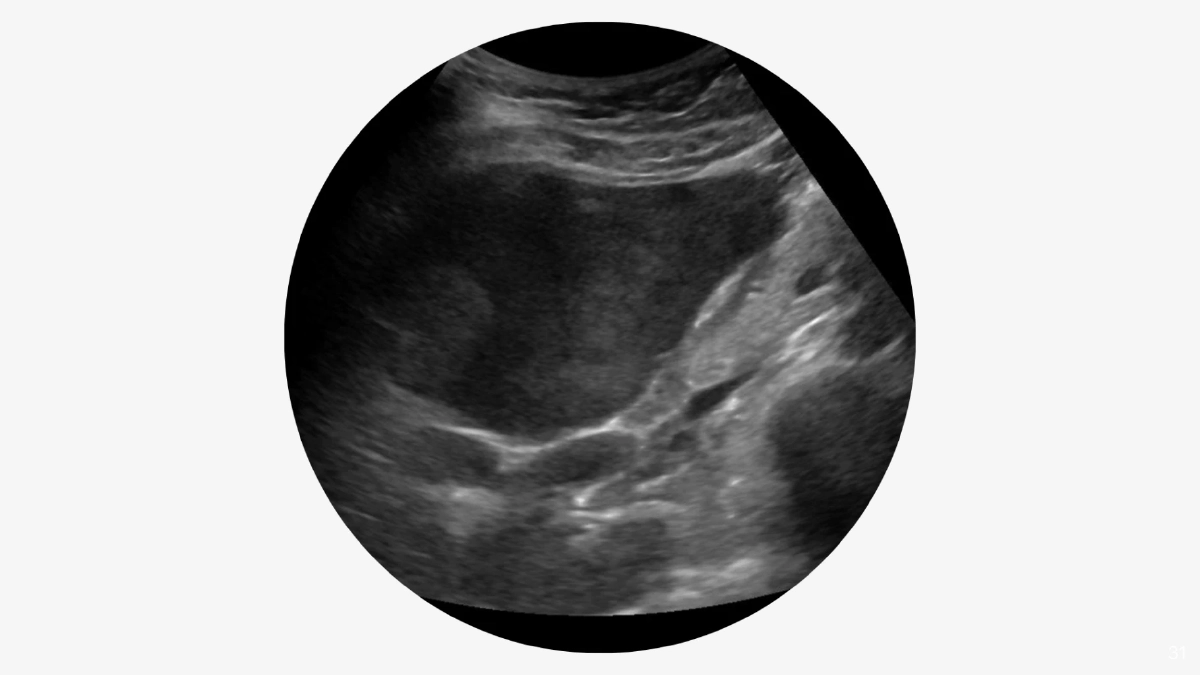

พวกเขาสร้าง SmartLiva ระบบ ‘AI อัจฉริยะ’ ทำงานเหมือนอัปเกรด ที่เปลี่ยนเครื่องอัลตราซาวด์ขาวดำธรรมดาๆ ที่มีอยู่แทบทุกโรงพยาบาล ให้กลายเป็นเครื่องมือวินิจฉัยประสิทธิภาพสูงเทียบเท่าเครื่องราคาล้านบาท สามารถอ่านภาพอัลตราซาวด์ได้แม่นยำและรวดเร็ว โดยแพทย์อัปโหลดภาพผ่านเว็บได้ทั้งบนคอมพิวเตอร์หรือแท็บเล็ต จากนั้นระบบจะช่วยปรับภาพให้ชัดขึ้น คัดเฉพาะบริเวณเนื้อตับที่ต้องวิเคราะห์

SmartLiva อัลตราซาวด์เสร็จใน 7 วินาที ด้วยความแม่นยำในการตรวจระยะตับแข็งสูงถึง 92% ตรวจเนื้อเยื่อผิดปกติได้แม่นยำ 87% และตรวจพยาธิใบไม้ตับได้แม่นยำถึง 84%